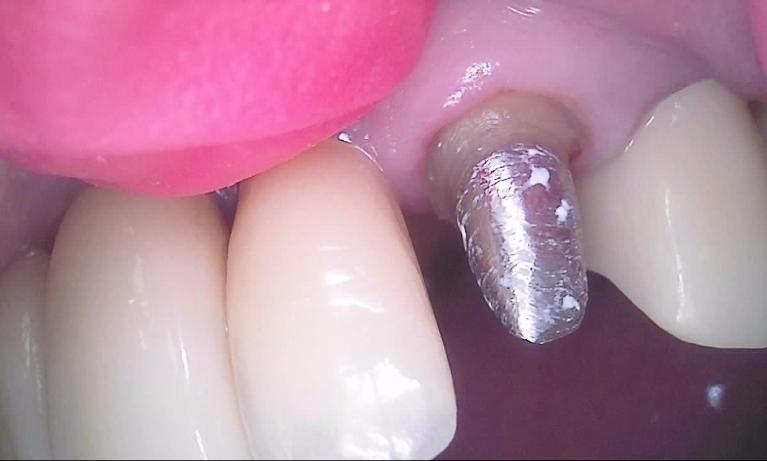

dental bridge | dental crown| palos heights ILWhat Does Placing a Crown or Bridge Involve?

A dental crown or bridge can usually be placed in two or three visits. First, we prepare your natural tooth to receive the restoration and then impressions are taken of your teeth. The impression accurately represents the position of your natural teeth so that your restoration fits perfectly.

The impressions are sent to a special dental lab, where they are used to create your permanent restoration, which usually takes about two weeks. Before you leave our office, we fit you with a temporary bridge or crown that you wear while the new crown or bridge is being prepared.

Once the restoration is finished, we will schedule an appointment for you to return to our office. At that time we check the finished restoration for proper fit, making adjustments as necessary. Finally, the restoration is cemented permanently into place.